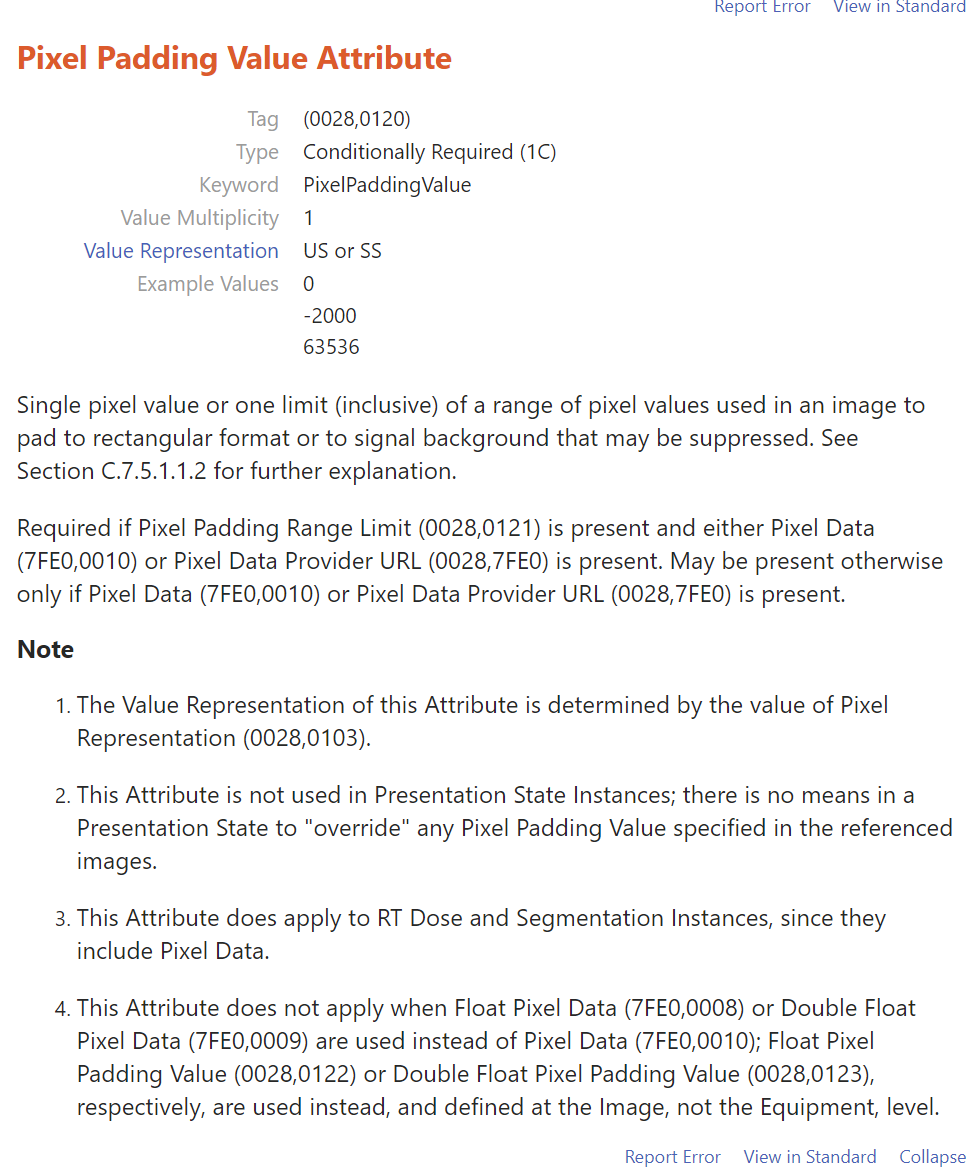

我们可以根据0028,0103内值来区分图像是否被填充过,如果pixel representation为0,则该CT图像未被填充过,其内部像素值都表示有效CT数值;如果pixel representation为1,则该CT图像内有两部分CT值,一部分是有效CT值,另一部分是填充值,只是为了把图像展示成矩形图像;

我遇到的这个数据中,0028,0103为1,则存在0028,0120值,其值为-2000。

我遇到的这个数据中,0028,0103为1,则存在0028,0120值,其值为-2000。

由于图像的斜率为1.0,截距为-1024,则-2000就会在线性变换后为-3024;

找一个背景值,可以看到该值为-3024;则像素值为-3024的像素即为填充像素,可以在后处理中过滤掉;

https://dicom.innolitics.com/ciods/rt-plan/general-equipment/00280120

https://dicom.innolitics.com/ciods/rt-plan/general-equipment/00280120